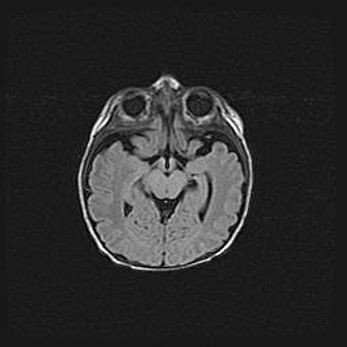

Сообщающаяся гидроцефалия. Кистозная энцефаломаляция головного мозга.

Возраст: 3 месяца 4 дня

Вес: 3100 г

Пол: женский

Окружность головы: 34 см

Срок гестации: 31 неделя

Кистозная энцефаломаляция головного мозга - одна из форм поражения головного мозга в детском возрасте. Характеризуется возникновением множественных и распространённых кист в коре, белом веществе и подкорковых образованиях головного мозга у плодов, новорождённых и детей раннего возраста. Развитие кистозной энцефаломаляции связано с внутриутробной асфиксией и гипотонией, родовой травмой, тромбозом синусов, пороками развития сосудов, инфекциями, сепсисом и другими причинами. Наиболее значимые инфекционные агенты: вирусы простого герпеса, цитомегалии, краснухи, токсоплазмы, энтеробактерии, золотистый стафилококк и другие.